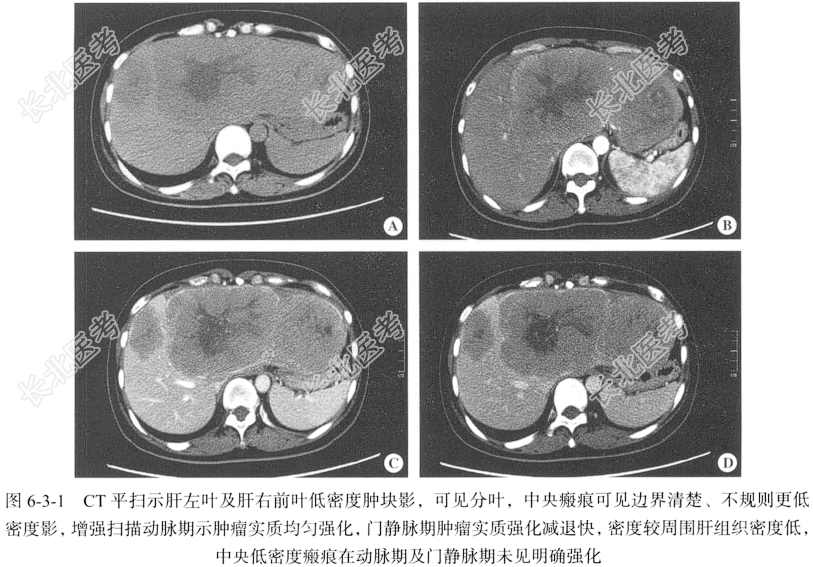

【影像图片】见图6-3-1。

【手术所见】肿块呈分叶状,切面呈灰黄色,见放射状纤维组织深入肿块内部,分隔肿块多呈结节状,纤维组织融合成纤维瘢痕,位于肿块中心,肿块内见点状坏死区,周围肝组织未见异常改变。

【病理所见】镜下见肿瘤呈大小不等、形状不规则的细胞巢,巢内细胞为嗜酸细胞,呈索状排列,被层状的纤维组织分隔,巢周见血窦(图6-3-2A)。肿瘤细胞分化良好,伴神经内分泌化,有丝分裂少见,细胞质丰富,呈颗粒状,细胞核增大,其内见巨大核仁,细胞巢之间见大量平行排列的板层状宽大胶原束并相互吻合,其中含有较多小血管(图6-3-2B)。

【病理诊断】纤维板层肝癌。